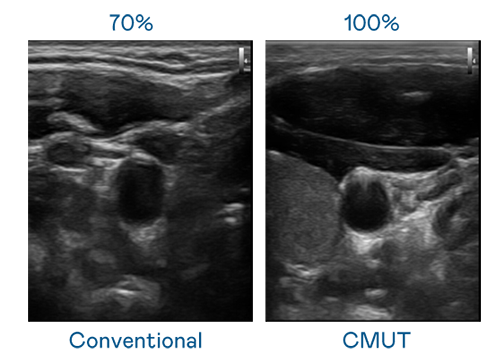

CMUT 技术是一种用电容式微机电元件来产生超音波讯号的技术。与传统 PZT 压电式技术相比,CMUT 频宽增加 30%,更宽频的超音波讯号让影像解析度大幅提升,是实现高影像品质医疗超音波扫描、促进精准医疗发展的关键技术。

超音波影像的解析度高低,首先取决于探头能发出的讯号频宽。伟德国际victor1946 CMUT 可提供高清晰的超音波讯号,提供高频宽、高灵敏度、影像纹理细节更高的超音波影像,协助医护人员缩短影像判读时间及利用精准的医疗影像进行诊断。